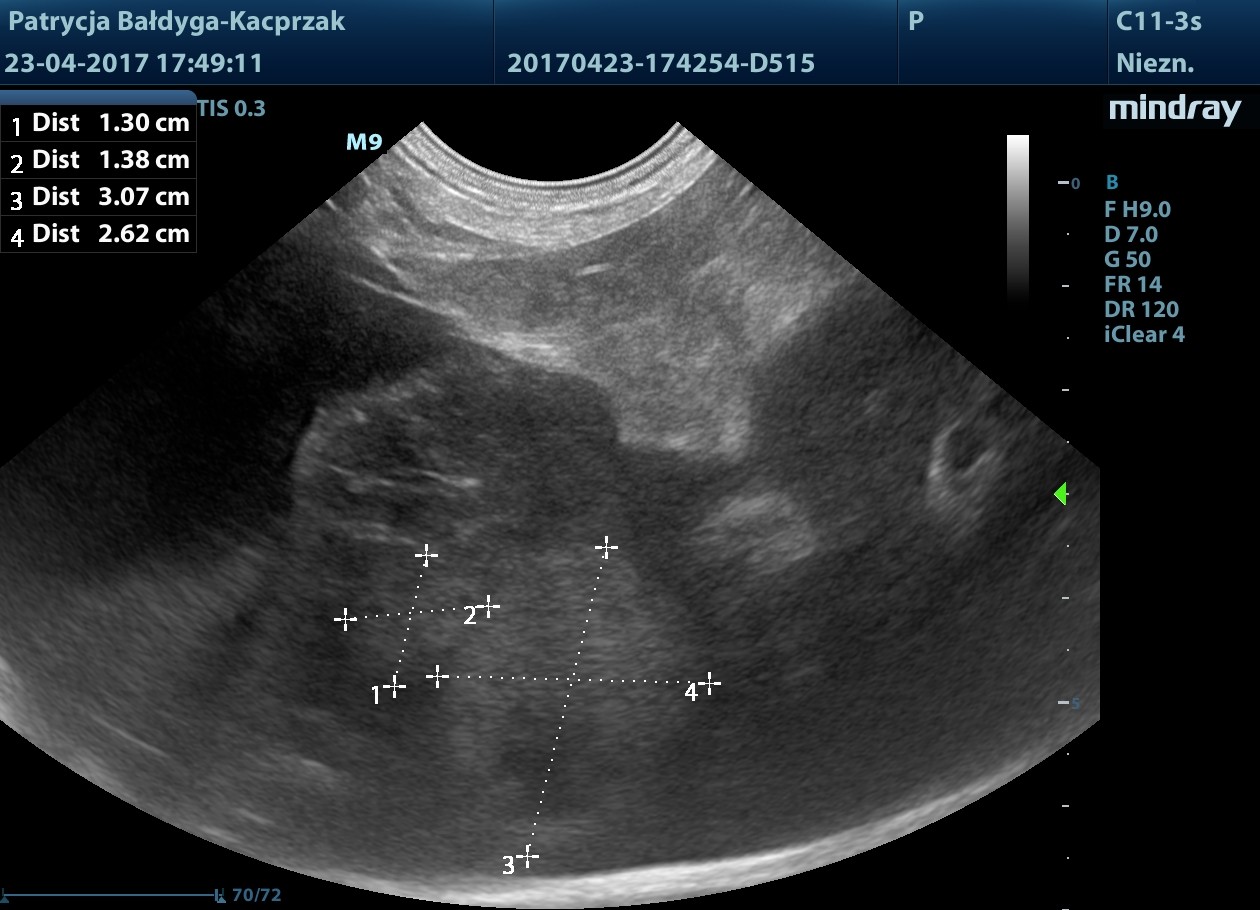

Kwiecień

Guz trzustki powiększył się

W płatach prawych wątroby widoczne nowe ogniska hiperechogenne, okrągłe ok. 13-31 mm, podejrzenie zmian metastatycznych

pod pęcherzykiem żółciowym zmiana ok 4,5 cm z drobnymi obszarami hiperechogennymi, jak zwłóknieniowymi/mineralizacyjnymi, gazem?

obrys 1- tu lekki cień akustyczny świadczący o twardości zmiany, obrys 2- tu artefakt rewerberacji, mogący sugerować obecność pęcherzyków gazu